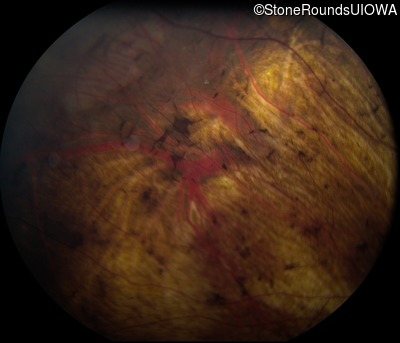

Fundus Photography - Left - 20/15 -2

Exemplar